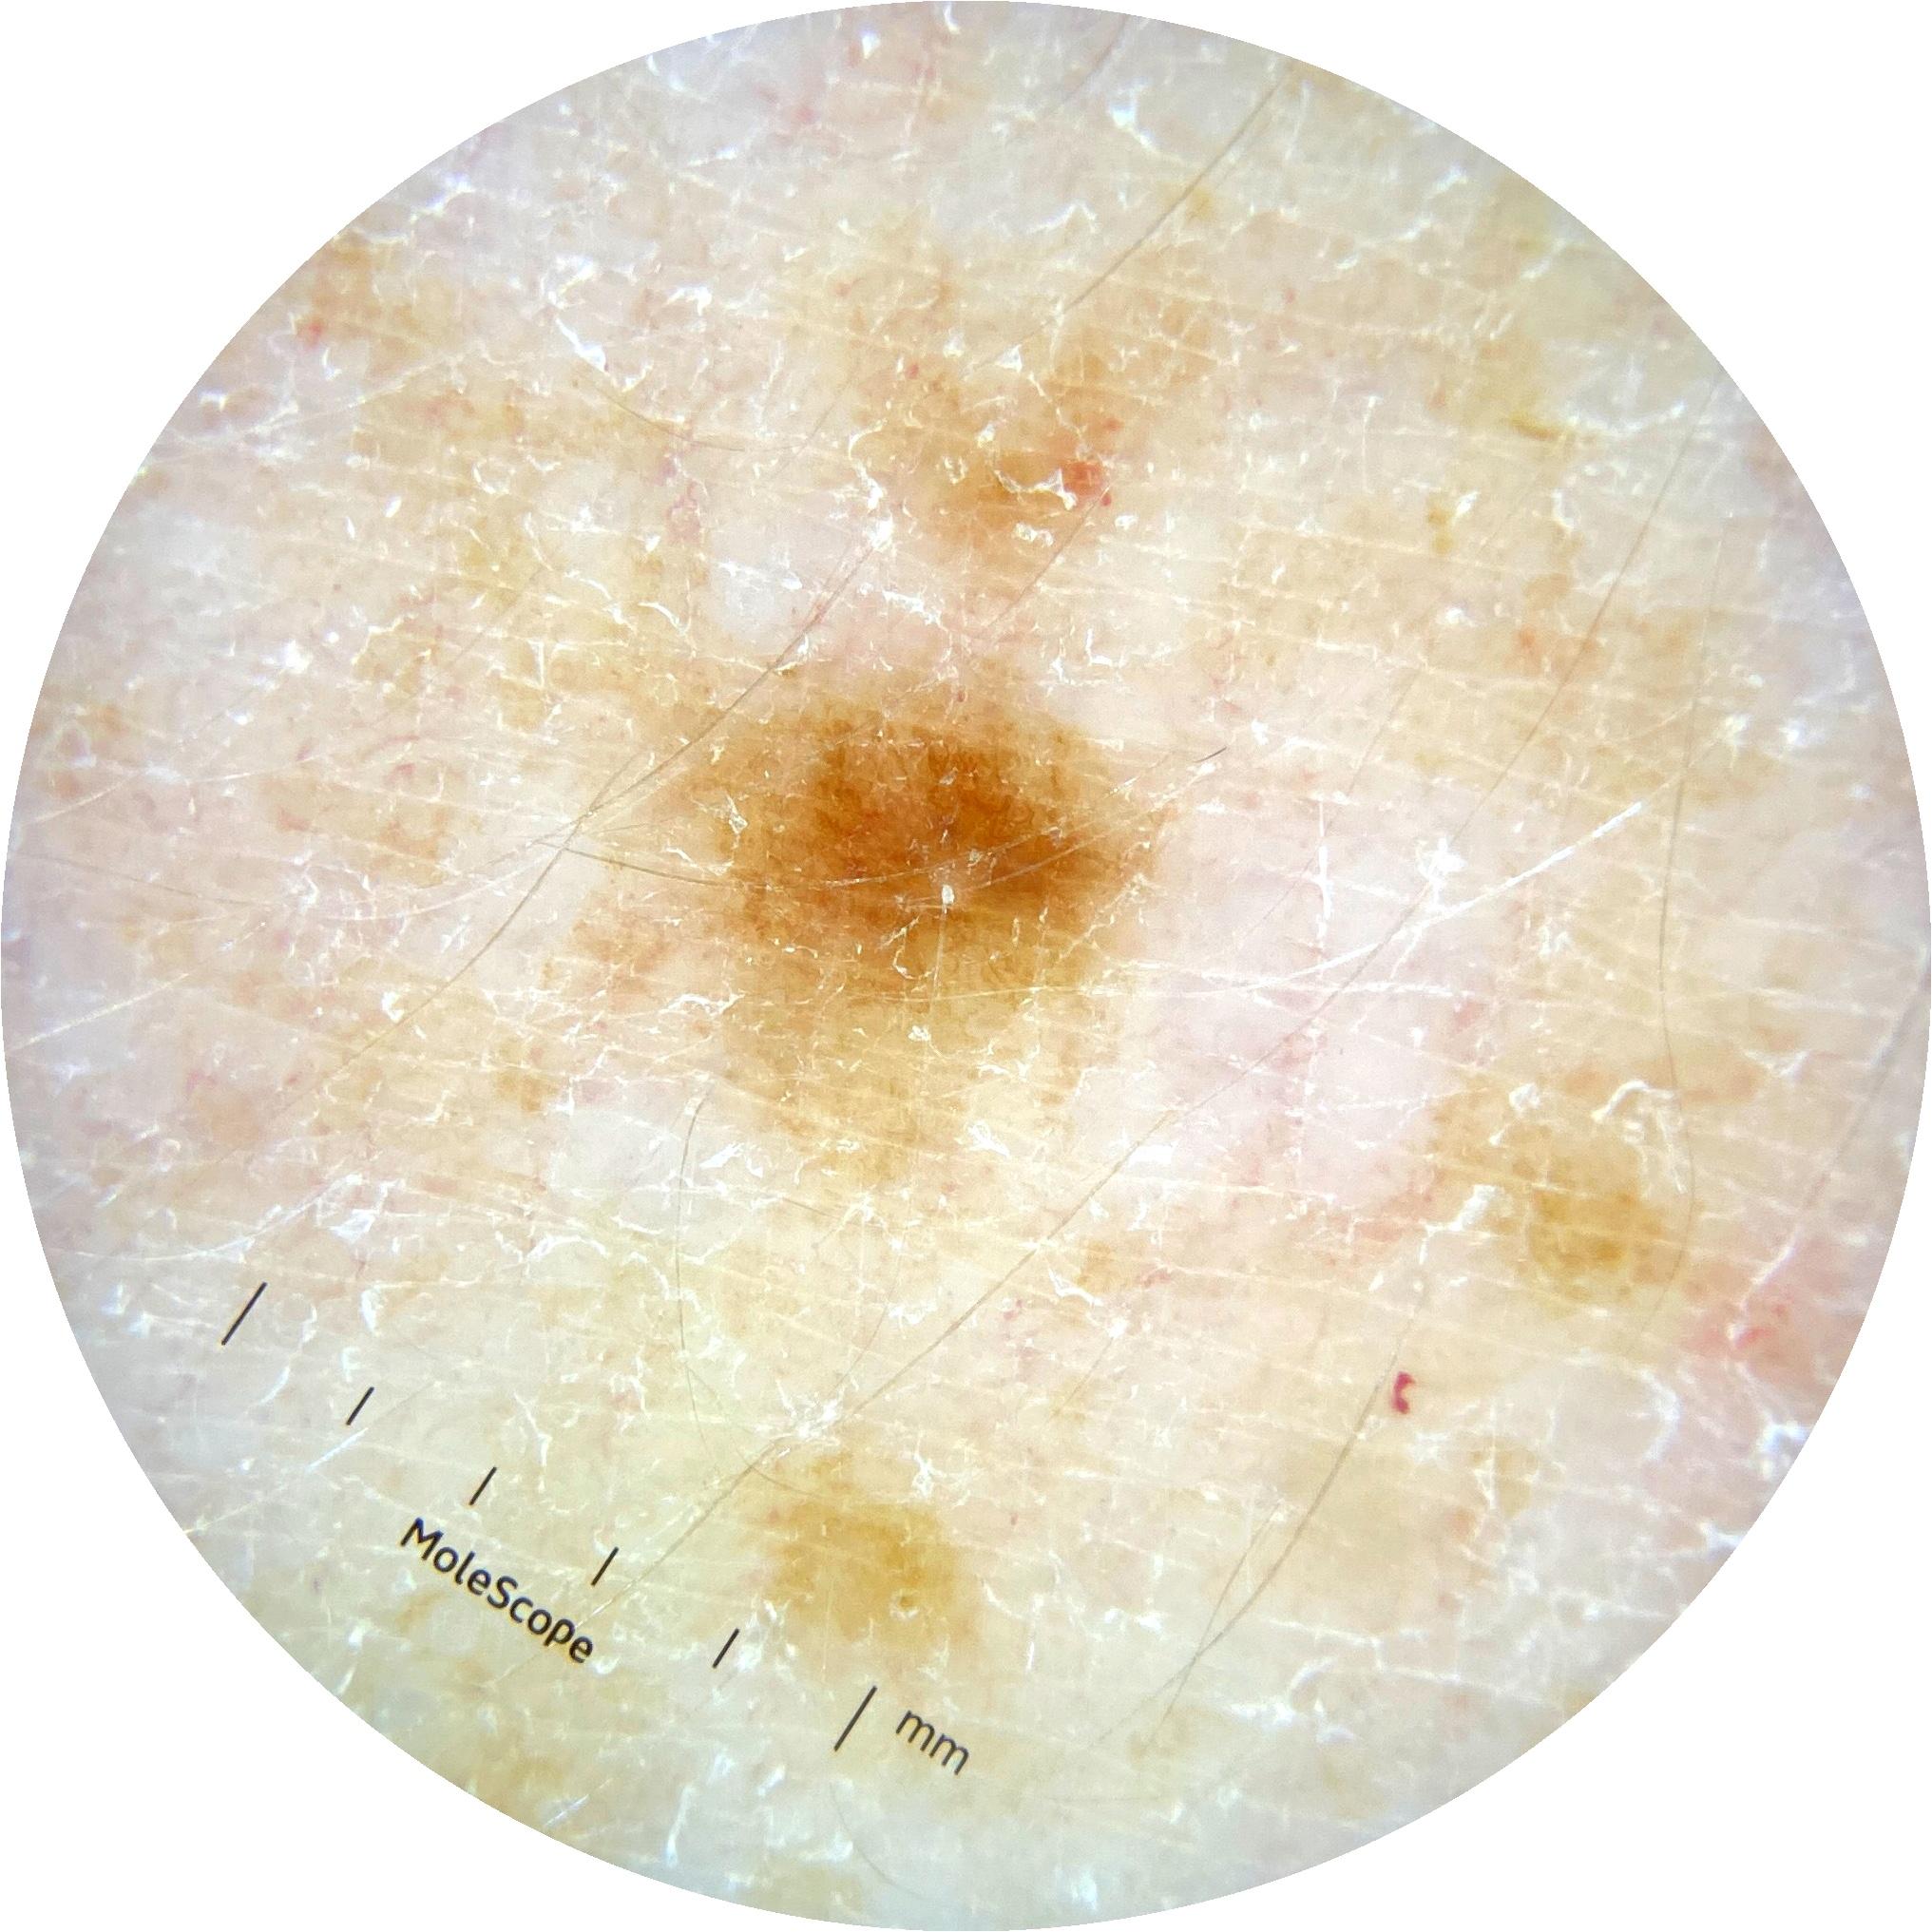

ISIC_1376863

2001 x 2001

MEL-SELF Trial, https://www.sydney.edu.au/medicine-health/our-research/research-centres/melself-project.html

Clinical

Field Value

acquisition_day 229

age_approx 40

anatom_site_general oral/genital

anatom_site_special oral or genital

concomitant_biopsy False

diagnosis_1 Benign

diagnosis_confirm_type single image expert consensus

family_hx_mm True

image_manipulation instrument only

image_type dermoscopic

lesion_id IL_8319447

patient_id IP_6274125

personal_hx_mm True

sex female